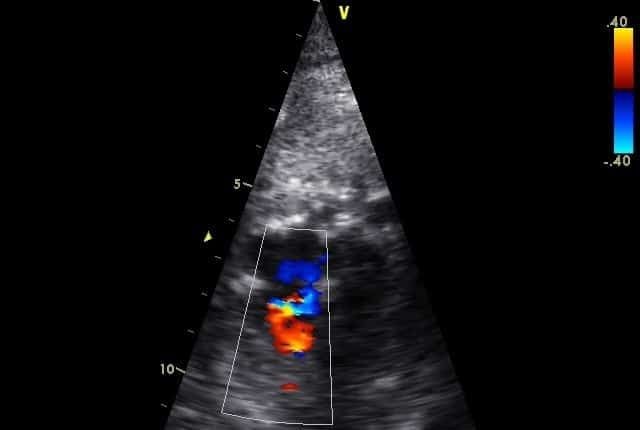

What is fetal echocardiography?

Fetal echocardiography is a test using ultrasound (sound waves) to study the structure, function and rhythm of your baby’s heart before birth.

Your obstetrician may obtain a general view of your baby’s heart during a routine pregnancy ultrasound. However, a fetal echocardiogram is a very detailed evaluation of your baby’s heart by a specialist in fetal cardiology.